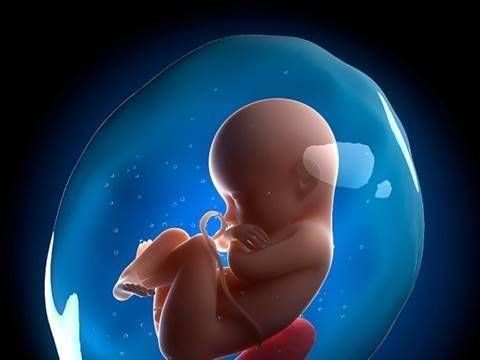

羊水不足对胎儿会造成什么影响?

羊水针对胎儿的作用有两个,一是保护胎儿,二是帮助胎儿完成循环。

文章插图

如果孕妈腹中羊水量不足,胎儿失去了悬浮保护,容易胎盘脱垂,或发生粘连,另外,羊水不足还会影响氧气的供应和循环,而这些因素这对胎儿的发育来说,是非常不利的。